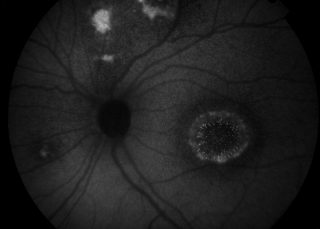

Retinal photography is the process by which a specialised camera is used to capture detailed images of the blood vessels and structures at the back of the eye, known as the retina. These images help clinicians to assess eye health, monitor disease progression, and document changes over time.

Retinal photography documents the back of the eye and shows the normal anatomical structures of the retina, including the veins, arteries, optic nerve head, macula, and fovea. These images provide clinicians with a detailed visual record of eye health.

If clinicians suspect that a patient may have complications related to a particular eye condition, retinal photography allows abnormal findings to be documented and monitored over time. This helps support diagnosis, treatment planning, and ongoing review.

Different imaging filters can be used to highlight specific structures at the back of the eye. These include red-free imaging, which enhances the visibility of blood vessels and nerve

fibre layers, and autofluorescence imaging, which helps assess the health of the retinal pigment epithelium and detect certain retinal diseases.

Central pole imaging focuses on the central retina, primarily documenting the optic nerve, macula, and fovea. This type of imaging is commonly used to assess conditions affecting central vision and optic nerve health.